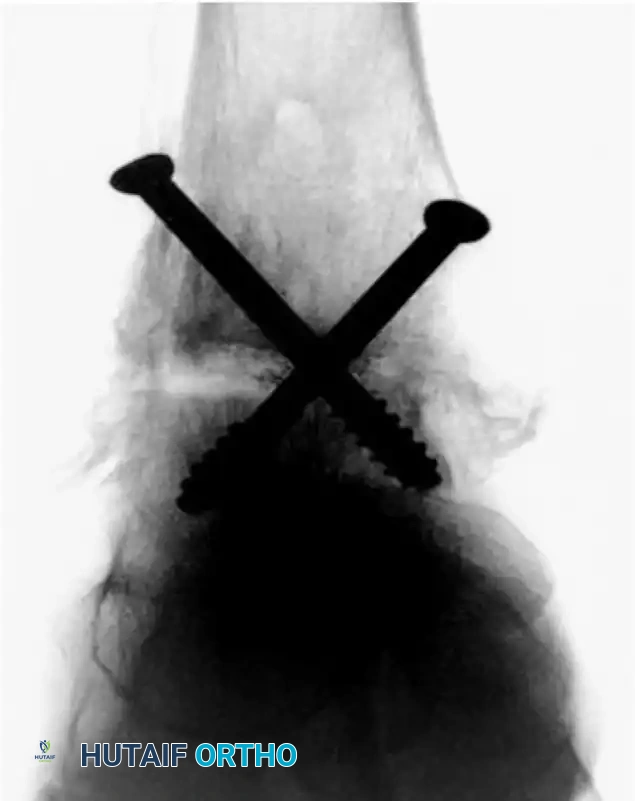

Image

FIGURE 50-12 Fixation with two 6.5-mm cannulated screws (Anteroposterior View).

As seen in the radiographic imaging (Figures 50-12 and 50-13), a standard crossed-screw configuration is employed.

* The First Screw (Home Run Screw): Typically directed from the posterior aspect of the distal tibia, aiming anteriorly and inferiorly into the neck of the talus.

* The Second Screw: Directed from the medial malleolus into the lateral aspect of the talar body.

* Optional Third Screw: If rotational stability is questionable, a third screw can be placed from the anterolateral tibia into the central talus.